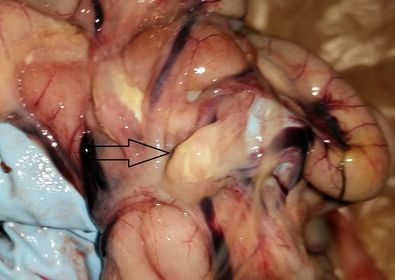

Intestines with tumors:

Gizzard with tumors:

Gizzard and intestine, both with tumors: